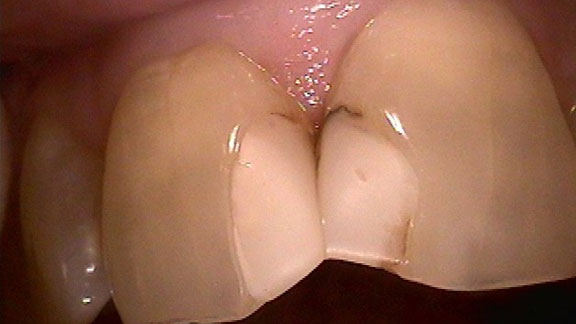

Lower Fixed RPD Implants